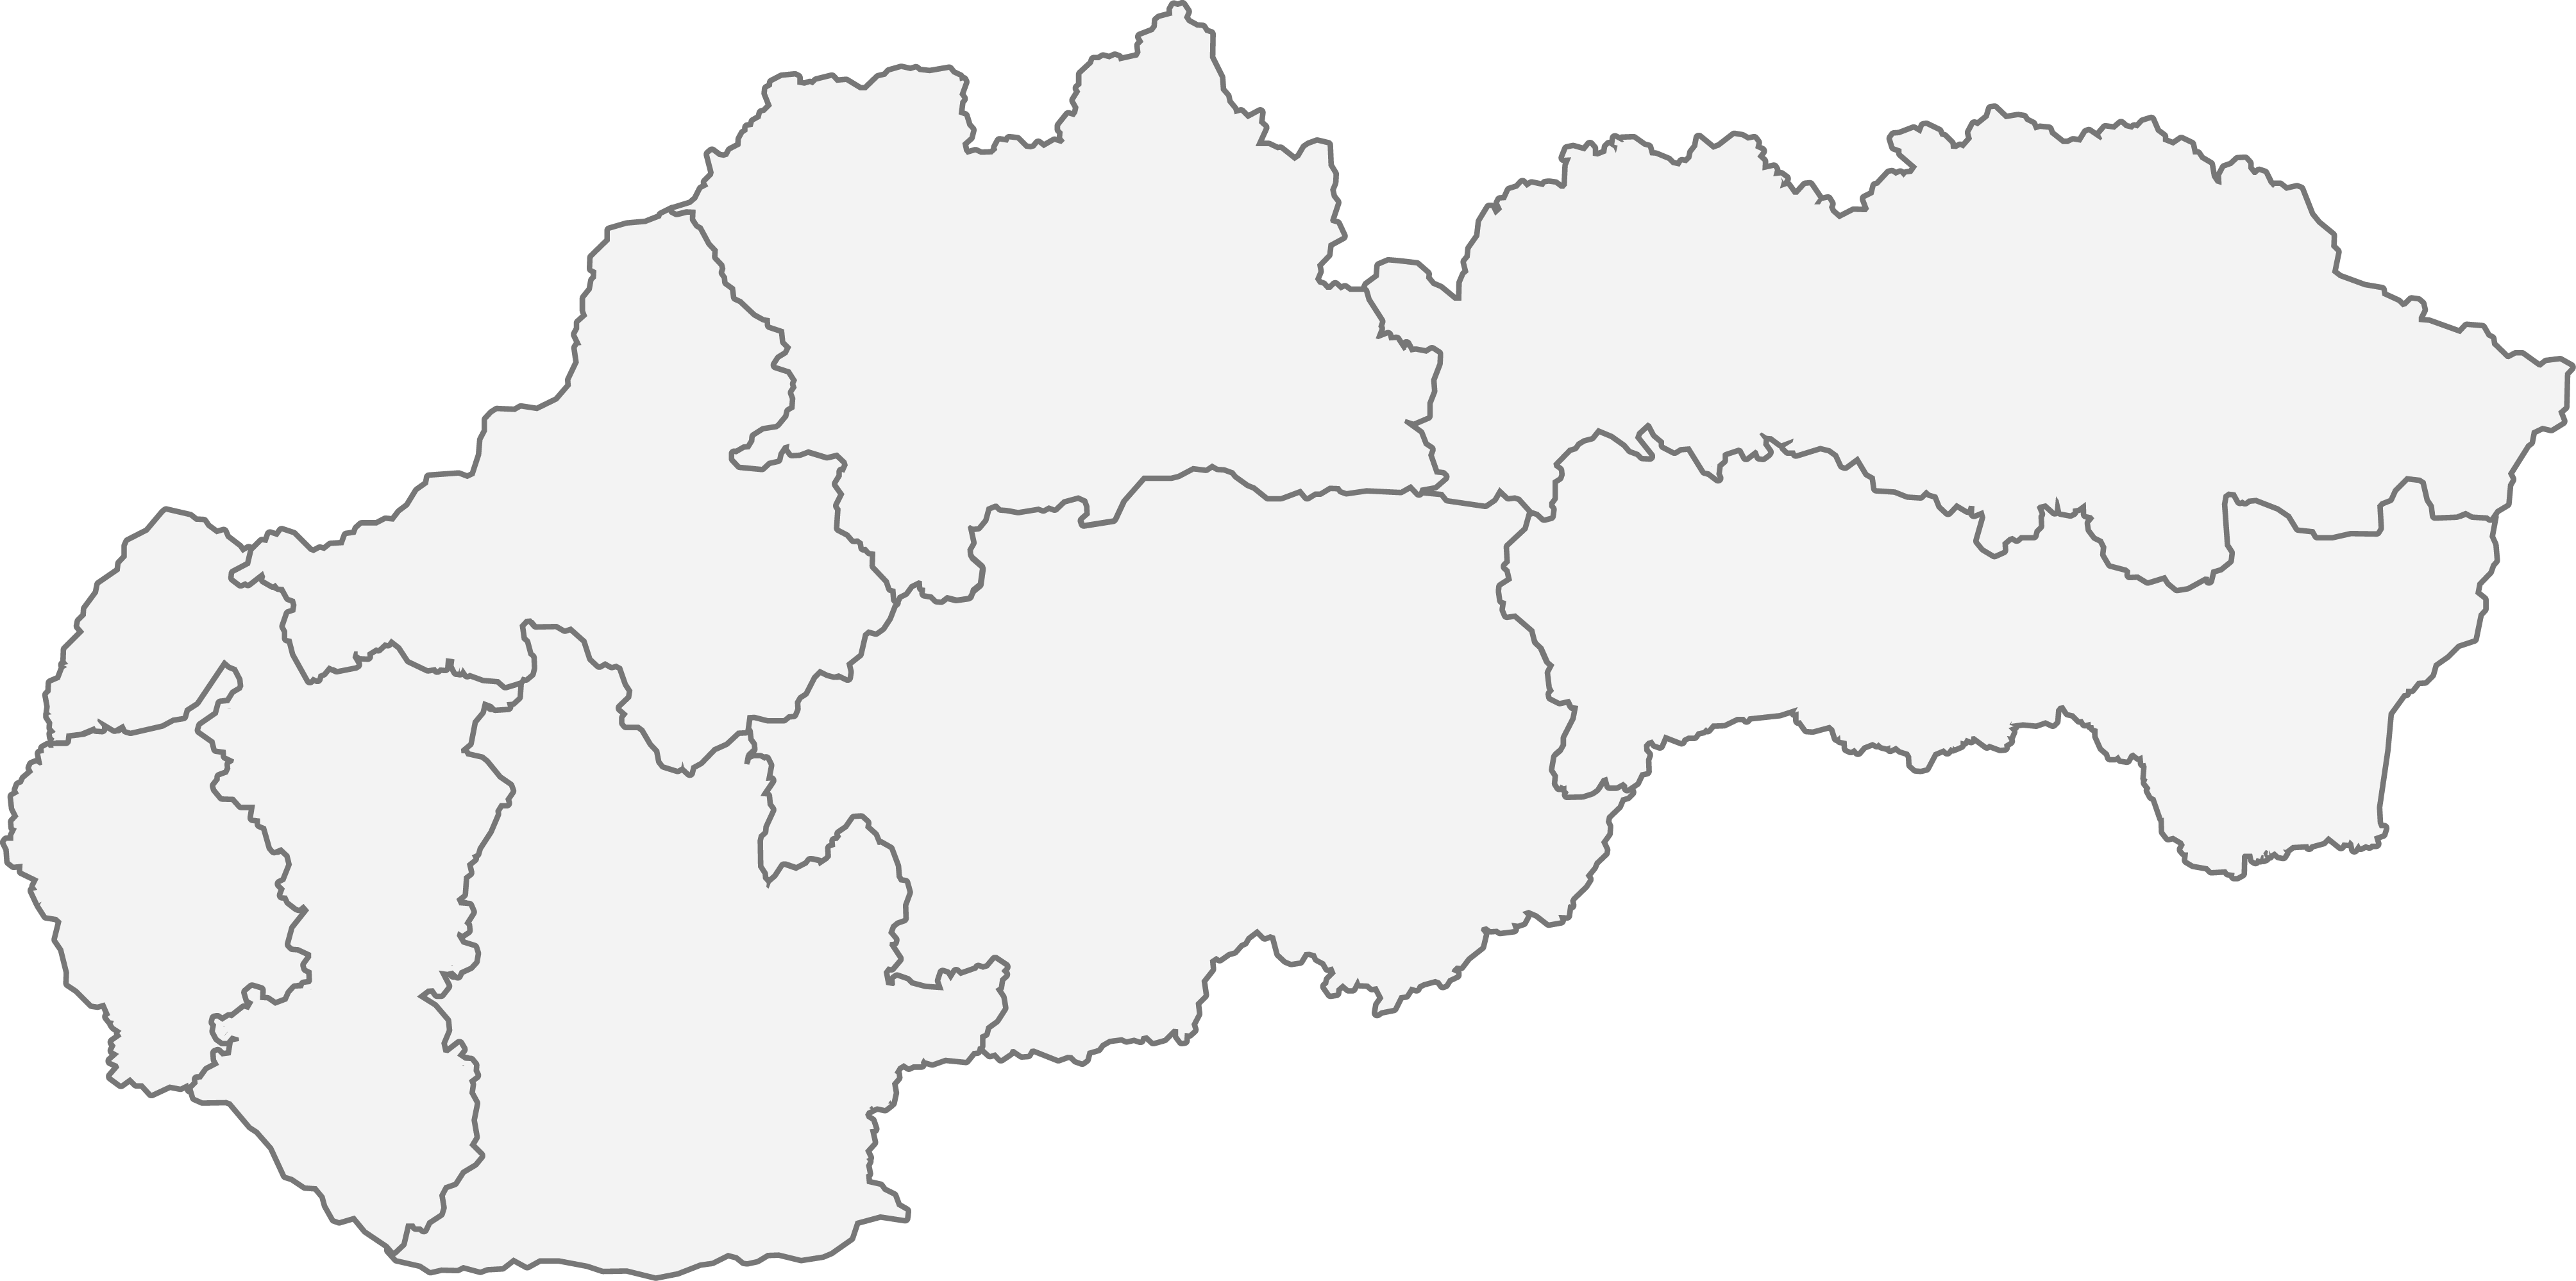

Pokiaľ sa váš zdravotný stav zhoduje s príznakmi ochorenia idiopatická pľucna fibróza, navštívte svojho všeobecného lekára, ktorý vás odporučí na vyšetrenie k odborníkovi – pneumológovi. Najbližšiu pneumologickú ambulanciu si môžete vyhľadať na tejto mape.